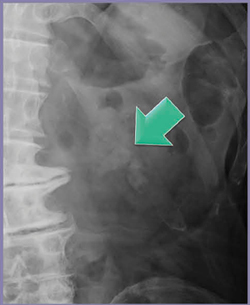

腎臓の腹部単純撮影(KUB)では,わずかに淡く左腎孟結石が描出されている(図2←)。Dual Energy Scanでは,135kVと80kVのCT値にはほとんど差がなく,尿酸結石であると推定された(図3)。

図2 症例1:腹部単純X線画像

わずかに淡く描出される左腎孟結石(←)